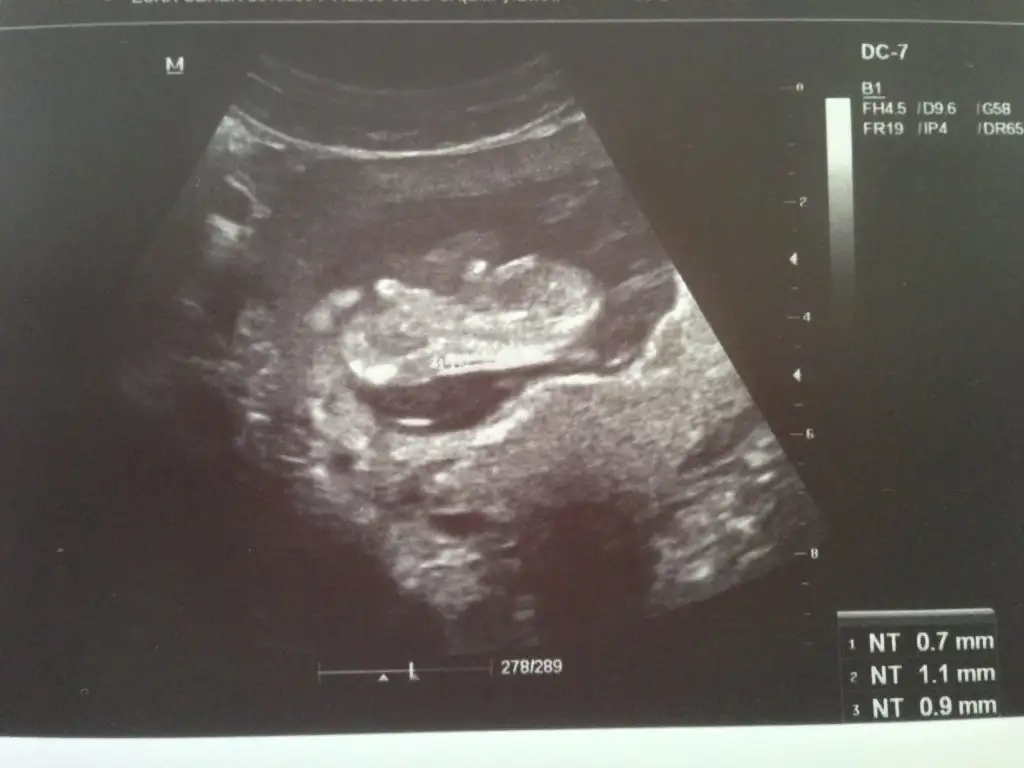

Dün cinsiyetini merak ederek doktora gittim 2 li tarama sonucu yüksek risk down sendromu çıktı amniyo sentez yolu göründü ilk bebeğimde de yaşamıştık çok sıkıntılı bir süreç inşallah olumlu sonuç alırız bu sefer değerler daha yüksek hayırlısı diyoruz

Dr birşey söylemedimi pekiKizlar 12+4 haftalikmis bebegim bakarmisiniz acaba tahminleriniz nedir ben anlayamadim

yorum yaparmısınız arkadaşlar .iki yeni resim daha yükledim lütfen yorumlarınızı bekliyorum